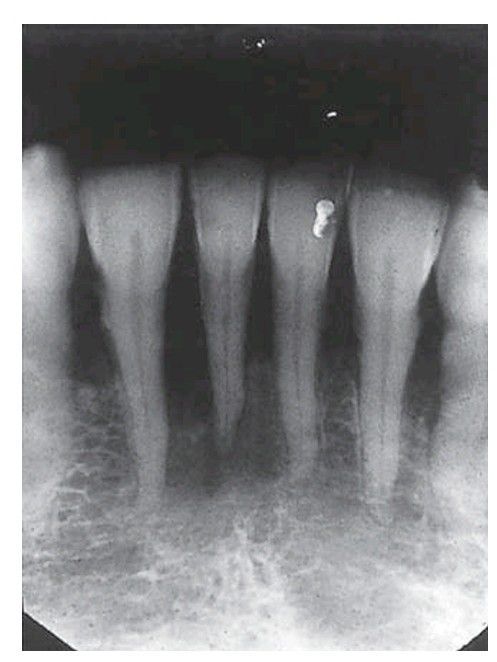

Hyperparathyroidism. A periapical view reveals the relative radiolucency of the bone. There is loss of lamina dura around the roots, loss of trabeculae centrally and coarsening of the trabecular pattern elsewhere.